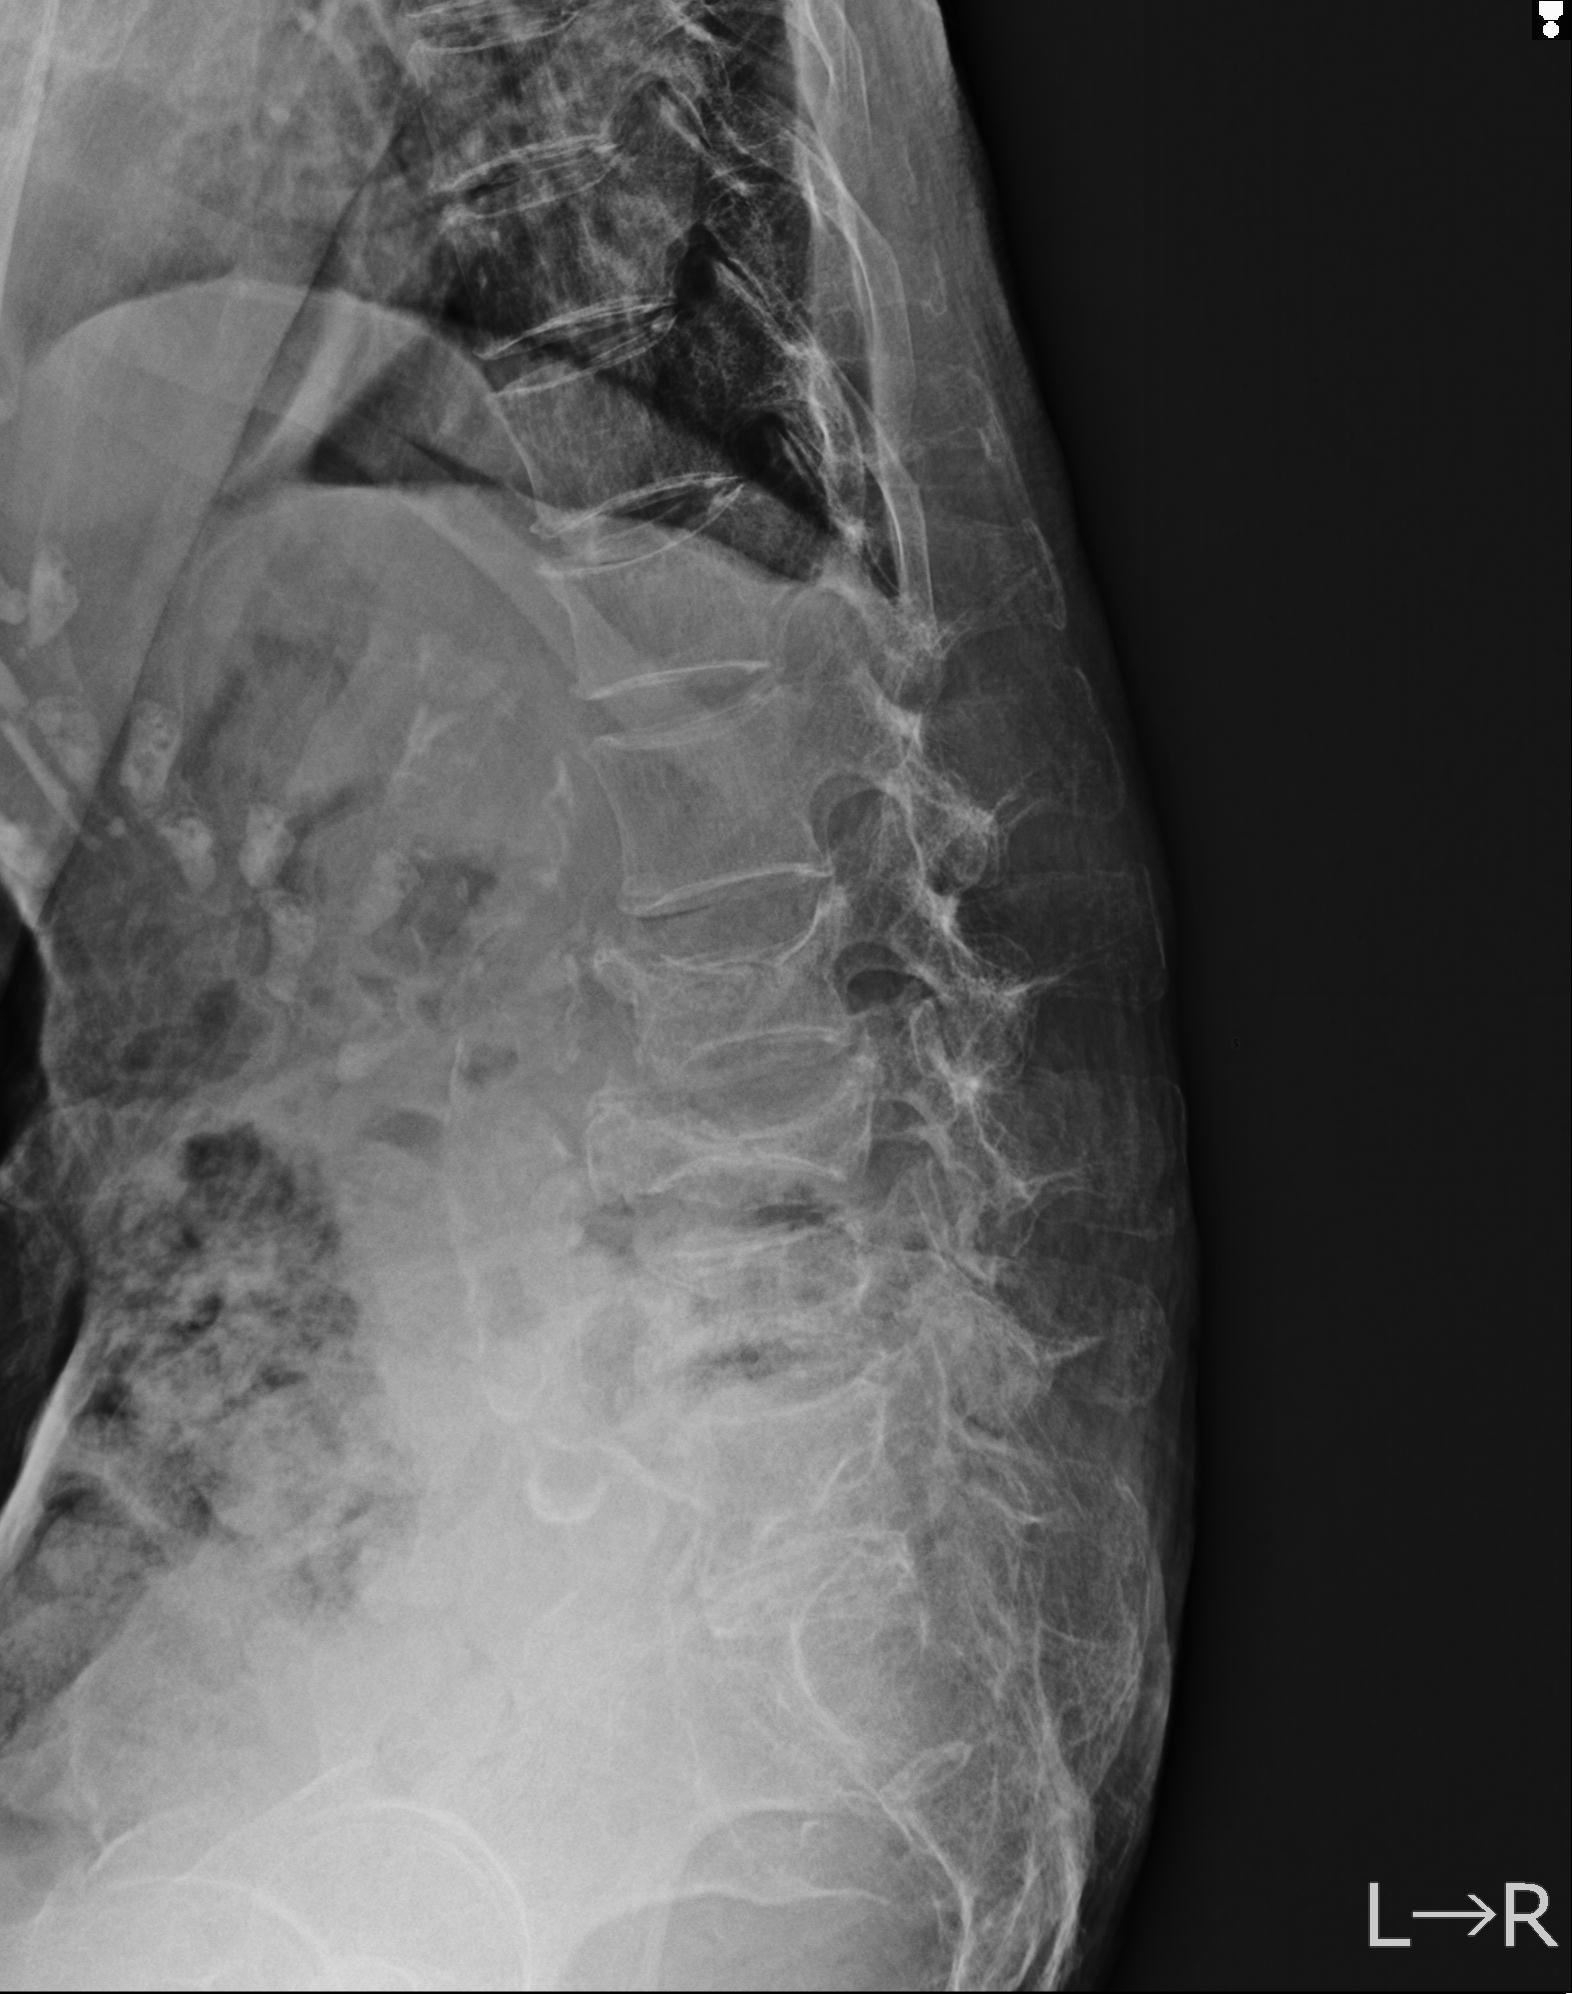

102755 1/4 2R 1/15 2R 右足関節 68歳女性 右三果脱臼骨折